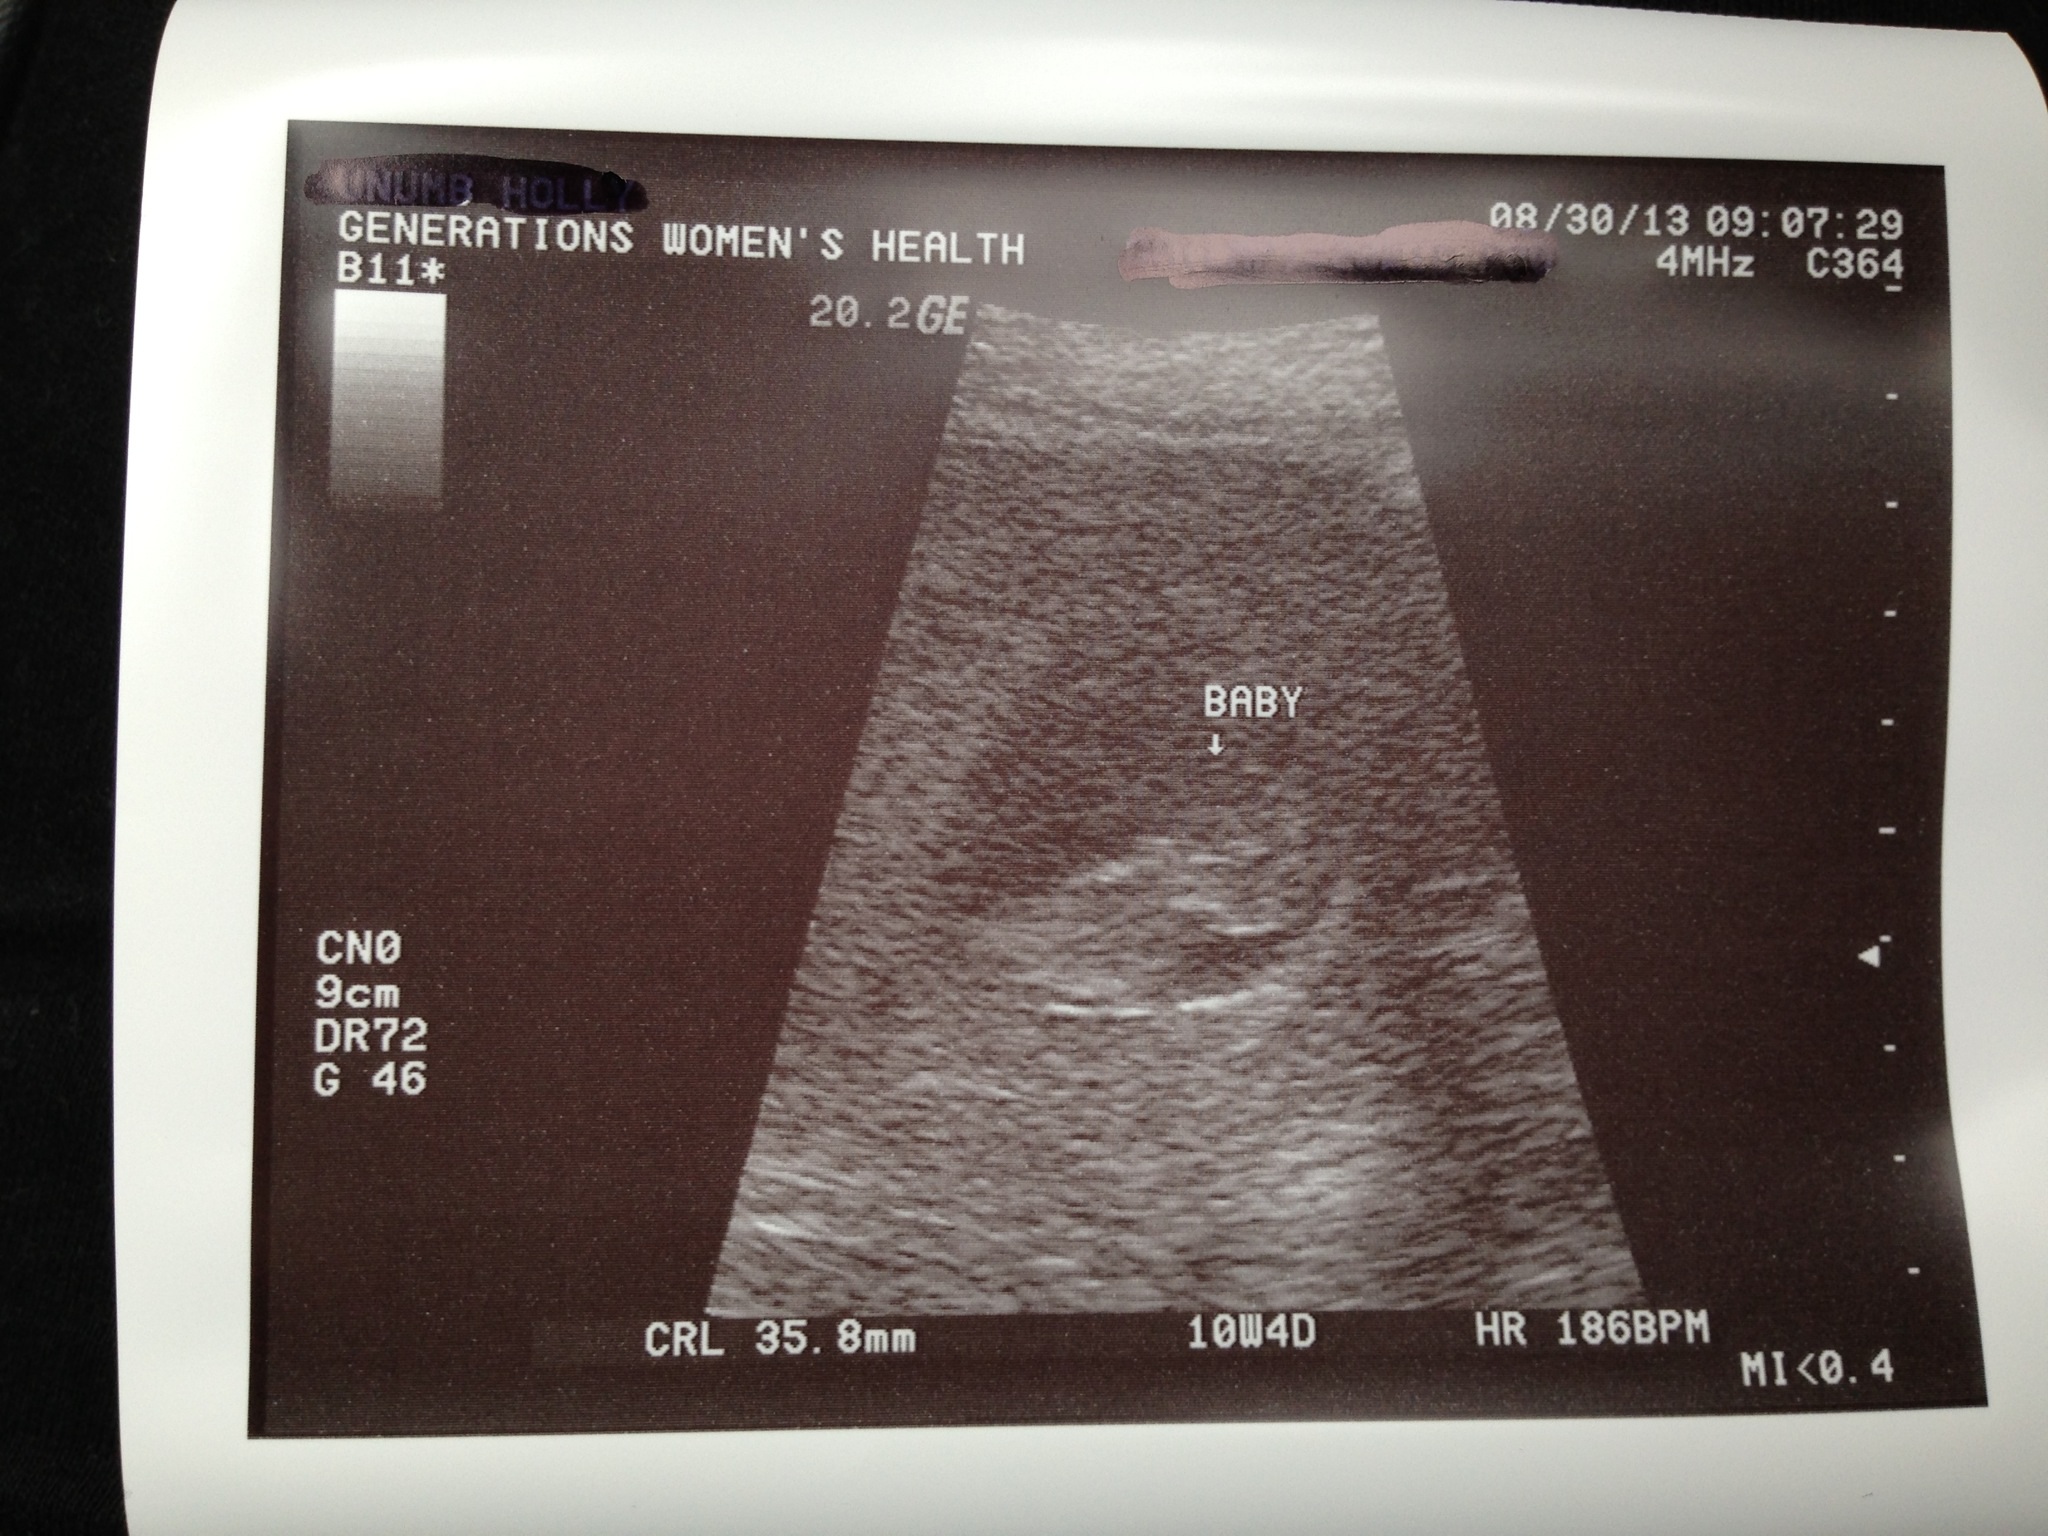

Surprise ultrasound :) 10w 4d

I went in for a physical and she tried to find the heartbeat with the Doppler and could find it so she snuck me in for an ultrasound!! So exciting! I measured 4 days ahead! It is so amazing to see baby moving and wiggling all around in there :) the heartbeat was at 186!

• Hb 186? Super ;)